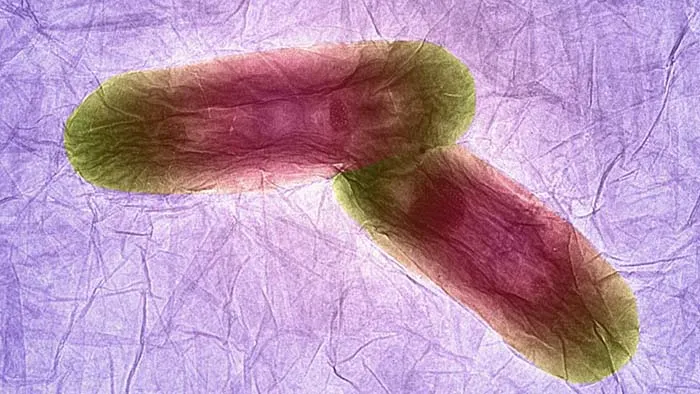

باکتری روی اکسید گرافین

گرافین مادهای است که تازه کشف شده و ضخامت آن تنها به اندازهی یک اتم است. تصویر بالا ضخامت بسیار کم آن را به خوبی نشان میدهد.

تضاد چین و چروکهای روی گرافین با این باکتریهای بیضی شکل به وضوح مشخص است. ما میدانیم که این باکتریها جانداران بسیار کوچکی هستند.

گرافین یک ورق بسیار باریک است و یکی از باریکترین و مستحکمترین مادههایی است که تاکنون کشف شده.

محققان سعی دارند که داروهای مختلفی را به آن بچسبانند تا بتوانند در صورت نیاز آن را در نقاط مختلف درون بدن قرار دهند.

طول این باکتریها حدود دو میکرومتر (۰٫۰۰۲ میلیمتر) است.